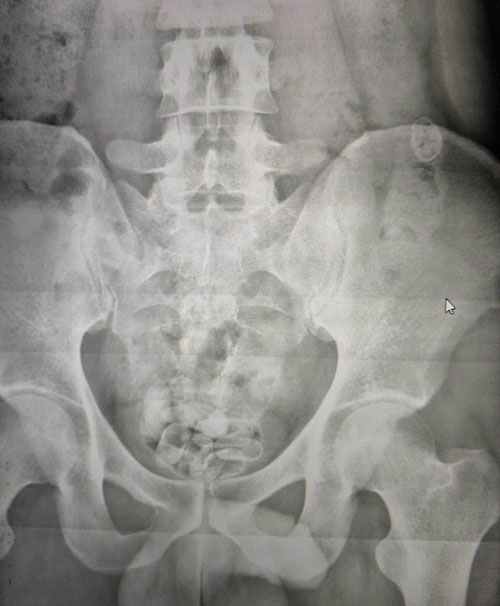

Röntgen filminde midesinde kapsül olduğu ortaya çıktı

Gözaltına alınan Afganistan uyruklu şüphelinin uyuşturucu maddeyi İran uyruklu Amir Hossein K. (27) ve Seyedgholam Hossein K.'den (30) temin ettiğini belirlendi. Bunun üzerine İran uyruklu şahısların ikamet ettiği eve de operasyon gerçekleştiren polis, yaptığı aramada 20 gram afyon sakızı, 33 adet metadon isimli uyuşturucu hap, 2,60 gram eroin ele geçirdi. Aramalar sırasında Amir Hossein K.'nin hareketlerinden şüphelenen polis, şahsı Karaman Devlet Hastanesine götürerek röntgen filmini çektirdi. Çekilen röntgen filminde şahsın midesinde kapsül olduğu fark edildi. Hastanede yapılan müdahale sonucu şahsın midesinden çıkarılan kapsüllerin içerisinden 30 adet metadon isimli hap, 15,30 gram eroin maddesi, 8 gram afyon sakızı ele geçirildi. Emniyeti götürülen 3 zanlı, sorgularının ardından adliyeye sevk edildi.